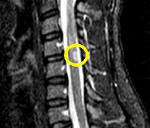

Из инструментальных методов применяются: рентгенография позвоночника для оценки состояния позвонков и межпозвоночных дисков, электромиография (исследование с магнитной стимуляцией, ЭМГ), с помощью которой оценивается прохождение электрического возбуждения по спинному мозгу; люмбальная пункция для исследования спинномозговой жидкости; МРТ позвоночника для визуализации спинного мозга; КТ позвоночника для визуализации костей позвоночника; КТ-ангиография для изучения кровеносных сосудов спинного мозга (выполняется с введением контраста).

Как только причину инфекционной миелопатии удается устранить, можно судить о том, каких результатов от лечения ждать. Важно определить, насколько болезнь повредила ткани спинного мозга, сохранилось или погибло его вещество. Это помогут сделать МРТ и электронейрография. Полное излечение возможно, если не было повреждения спинного мозга. Если заболевание продолжает развиваться, очаг инфекции не устранен, возможна полная потеря трудоспособности.